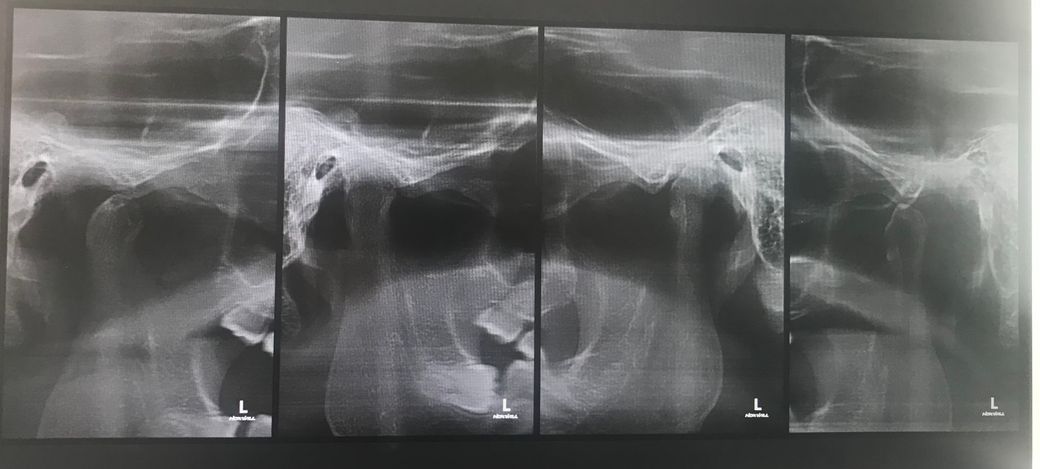

턱관절 엑스레이 마모 상태좀 봐주세요

구강내과 총 3곳은 마모가 아니라고 하는데 맞나요? 입벌릴땐 괜찮은데 입 크게 벌리고 다물면 바스락 거리면서 관절 사이가 너무 아파요 666운동하면 너무 아픈데 안하는게 맞겠죠?

관리를 어떻게 해야하는건지.... 죽 먹을라고 숟가락 넣어도 아파요 병원은 모두 정상이라고만 하고 아시는 선생님 부탁드려요

골관절염은 아닌 것으로 보여집니다. 다만 현재 통증이 있다면 해당 부위에 염증은 있는 것이 맞습니다. 또한 마모가 아니더라도 턱관절 주위에 있는 디스크가 재위치가 되지 않았다면 턱이 움직이면서 바스락 거리는 소리가 날 수 있습니다. 현재로서는 염증을 먼저 잡아야할 것으로 보이며 염증 위치가 판단이 된다면 악관절 세척술 등을 하거나 일상 생활 속에서 턱 사용을 자제해야 할 것으로 보여집니다.

관절염과 같은 뼈의 마모는 관찰되지 않습니다. 입을 크게 벌리는 행동은 자제하셔야 하고 정확한 진단을 위해 대학병원을 방문해보시는 것이 좋아보입니다